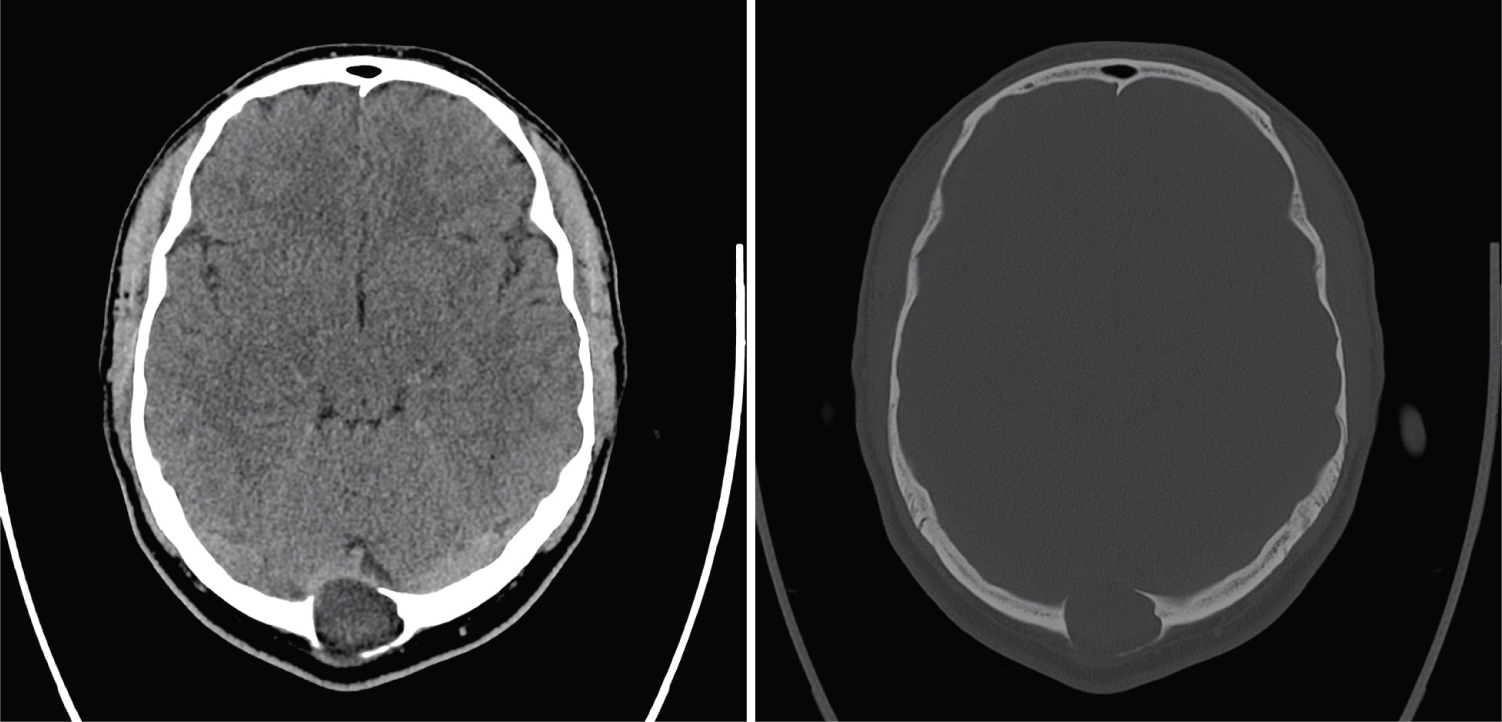

In our case, the patient was an adult, diagnosed with a palpable mass at his occiput, which was proven to be an intraosseous epidermoid cyst, compressing on the confluence of the sinuses, causing increased ICP and visual symptoms and papilloedema. It is advisable for scalp lesions, especially overlying important anatomical structures, to perform brain imaging, before attempting excision (Figure 1, Figure 2, Figure 3 and Figure 4).

Figure 1: Axial CT. A) Hypodense intra-osseous lesion at the level of the torcula; B) Image at the same level with reconstruction in bone algorithm clearly shows the expansile nature of the lesion with thinning of both the internal- and external table of the skull. View Figure 1